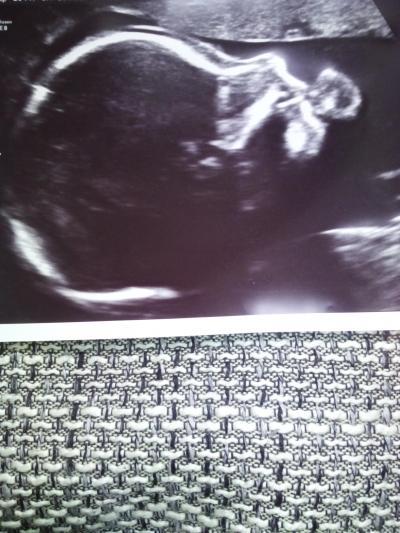

Hallo ihr Lieben. Bin von der Feindiagnostik zurück und mit meiner kleinen Maus ist alles ok. Sie ist zeitgerecht entwickelt und auch sonst gibt es keinerlei Auffälligkeiten. Die Kleine ist laut Befund stolze 23 cm gross und 350 Gramm schwer. Ein Bildchen habe ich mit angefügt, da lutscht sie grad am Unterarm.

Bild zu Feindiagnostik - Forum für März - Mamis